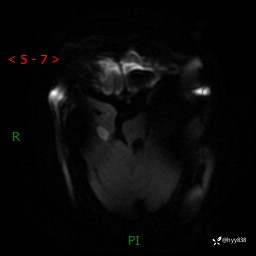

颅脑MRI(T2WI+DWI)